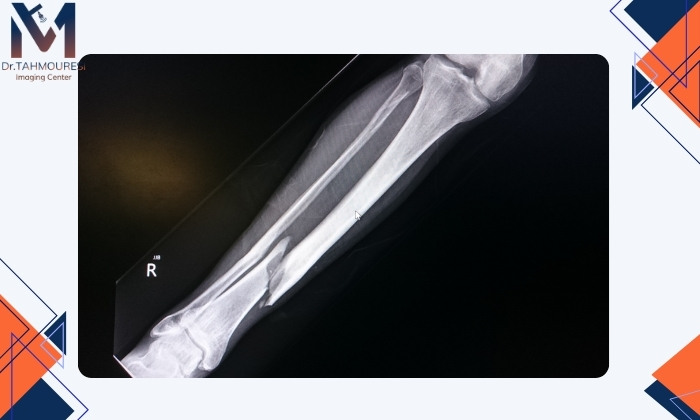

تشخیص شکستگی استخوان با عکس ساده

شکستگی استخوان همیشه با عکس ساده (رادیولوژی) مشخص نمیشود. رادیوگرافی در بیشتر موارد مخصوصاً در شکستگیهای واضح یا استخوانهای بزرگ (مانند بازو، ساق و ران) عملکرد خوبی دارد. اما در برخی انواع شکستگیها ممکن است تصویر واضحی در عکس دیده نشود.